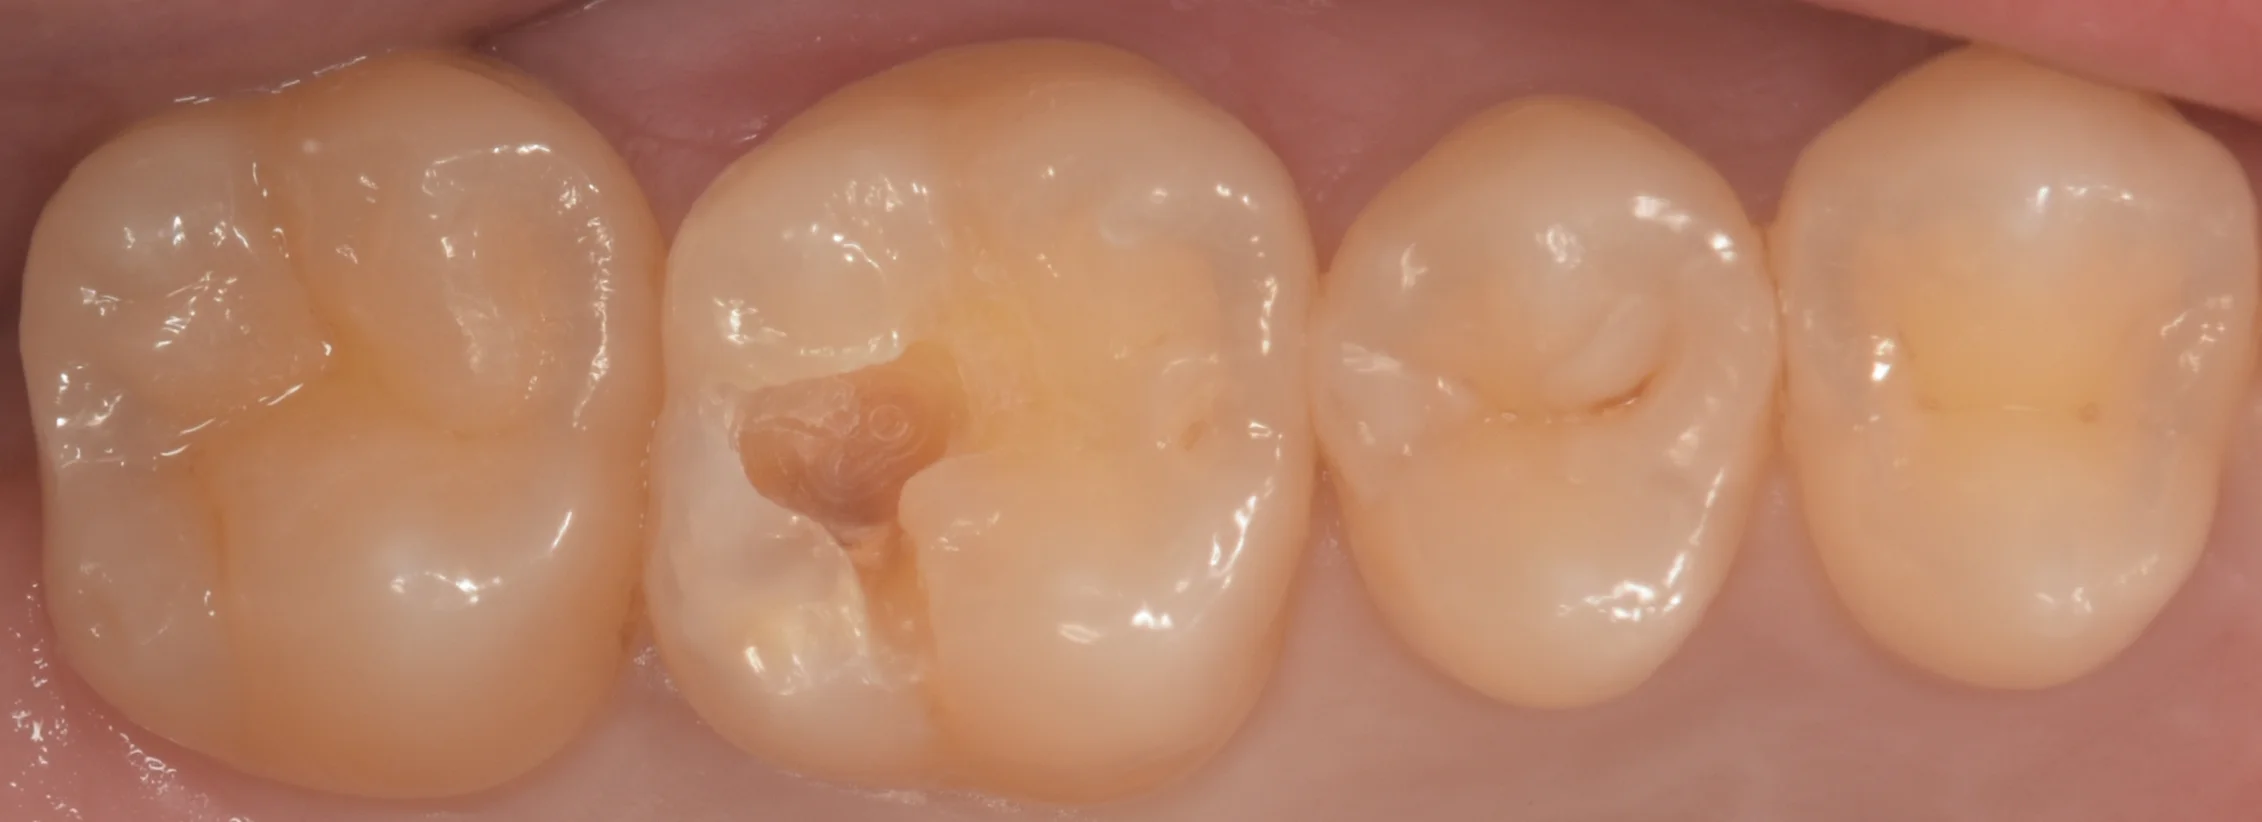

まずは術前からです。

今回は画面上の左から2番目の歯を治療しています。

元々は保険の白い詰め物が入っている状況ですね。

こちらは1年ほど前にレントゲンで確認した際には虫歯にはなっていなかった歯なのですが、今回レントゲン診査をした際に虫歯になっているのが確認できたため、介入と至りました。

古い詰め物を除去したのがこちらの写真になります。

やや黒くなっているのが分かりますかね?

さらに古い詰め物を取って光が通りやすくなったため、虫歯が内部で広がっているのが透けて、見た目でも分かります。